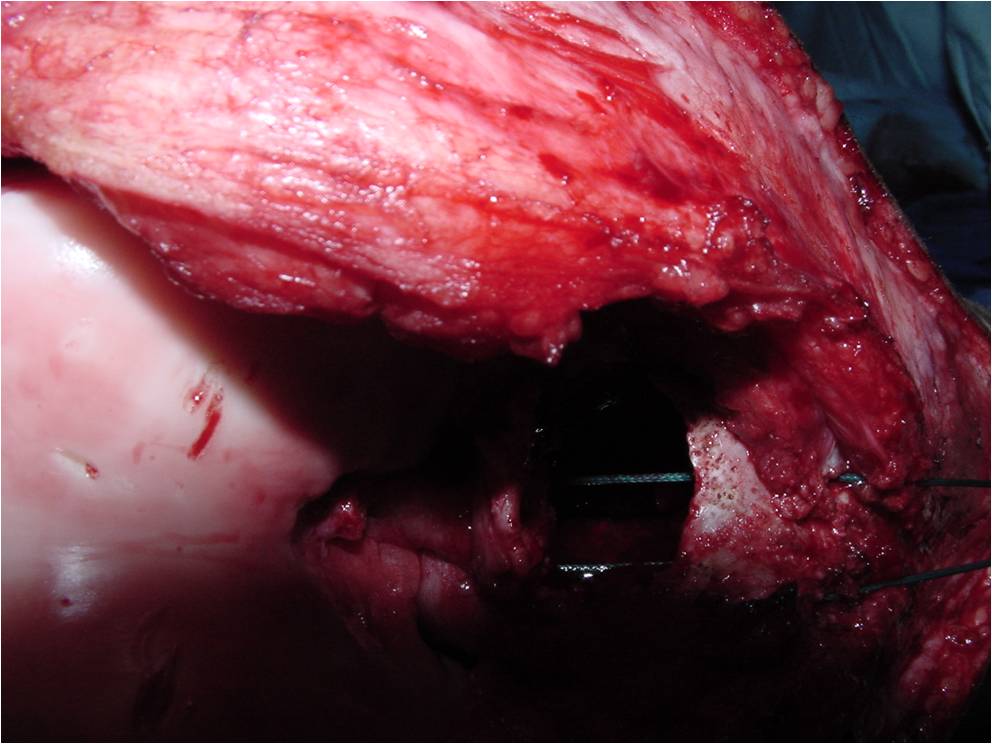

Treatment of a Chondroblastoma of Proximal Humerus with Intralesional Curettage Resection, Cryosurgery and Bone Grafting

- intralesional curettage resection and bone grafting most common treatment

- Cement and internal fixation may also be used to fill the defect after removal for selected patients

- Local adjuvants such as cryosurgery (liquid nitrogen application) may be considered to decrease the risk of local recurrence